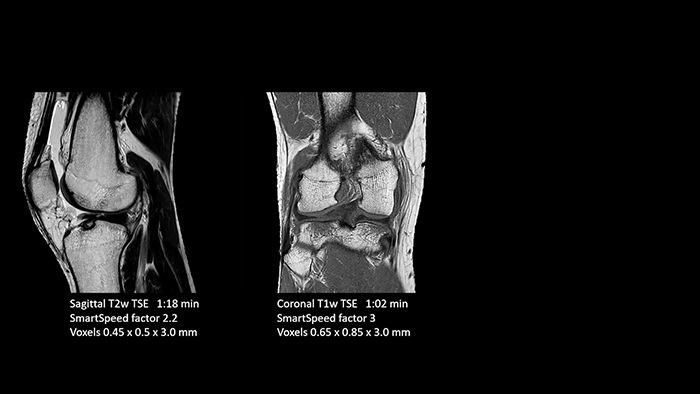

With SmartSpeed also scan times for diffusion imaging and motion-free imaging can be reduced. Scanned without contrast agent. Performed with 1.5T Ambition X, dS Torso coil.